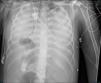

Mujer de 19 años, con antecedente de miopatía de Steinert, intubada por distrés respiratorio grave tras laparotomía exploradora por seudooclusión intestinal. En aspirado traqueal, E.coli sin mecanismos de resistencia. Muy mala mecánica pulmonar (compliance inferior a 2ml/cmH2O) y sin respuesta a maniobra de prono, se canula ECMO veno-venoso y, ante las altas presiones en la vía aérea con 4ml/kg de peso ideal, se cambia ventilación por ventilación con liberación de presión en la vía aérea (APRV): presión alta 15cmH2O; tiempo alto 6s; tiempo bajo 0,3s. Inicialmente 10ml de volumen espirado. La evolución radiográfica se muestra en las imágenes (fig. 1: día0; fig. 2: día2; fig. 3: día5). Este caso es un ejemplo de cómo la ventilación por APRV mientras aseguramos el intercambio gaseoso con el ECMO puede ser útil en el manejo de pacientes con distrés respiratorio refractario.